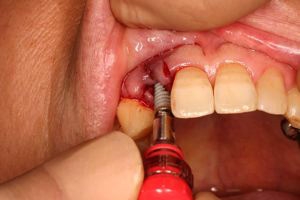

抜歯を行う。折れていた位置がかなり深い位置であるのがわかる。

歯根も抜歯

抜歯した穴をよく掃除(掻爬)後すぐにインプラントを埋入

埋入直後のレントゲン。上部に見えるのは抜いた歯を利用して両どなりの歯に接着して一時的に使えるようにした。